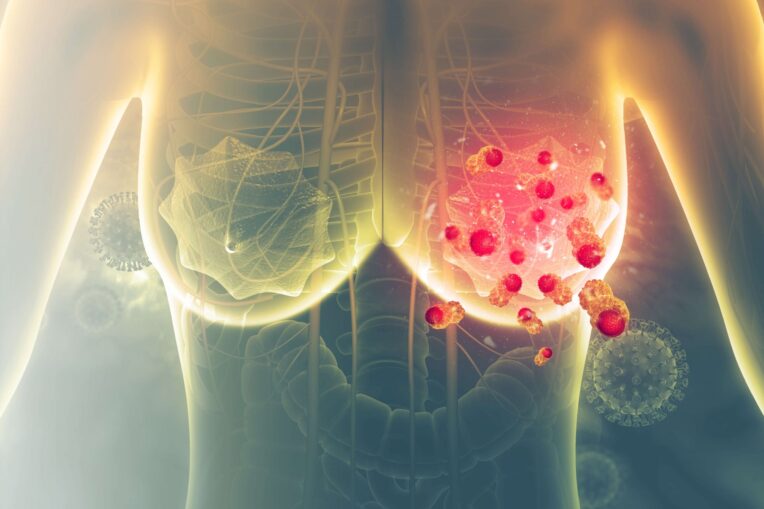

Breast cancer begins when there is an uncontrollable growth of breast cells or mutations caused within them, this creates a mass in the breast tissue, also referred to as a tumor. Much like other cancers, breast cancer can grow and move to other parts of the body and create new tumors; when this occurs, it Is called metastasis.